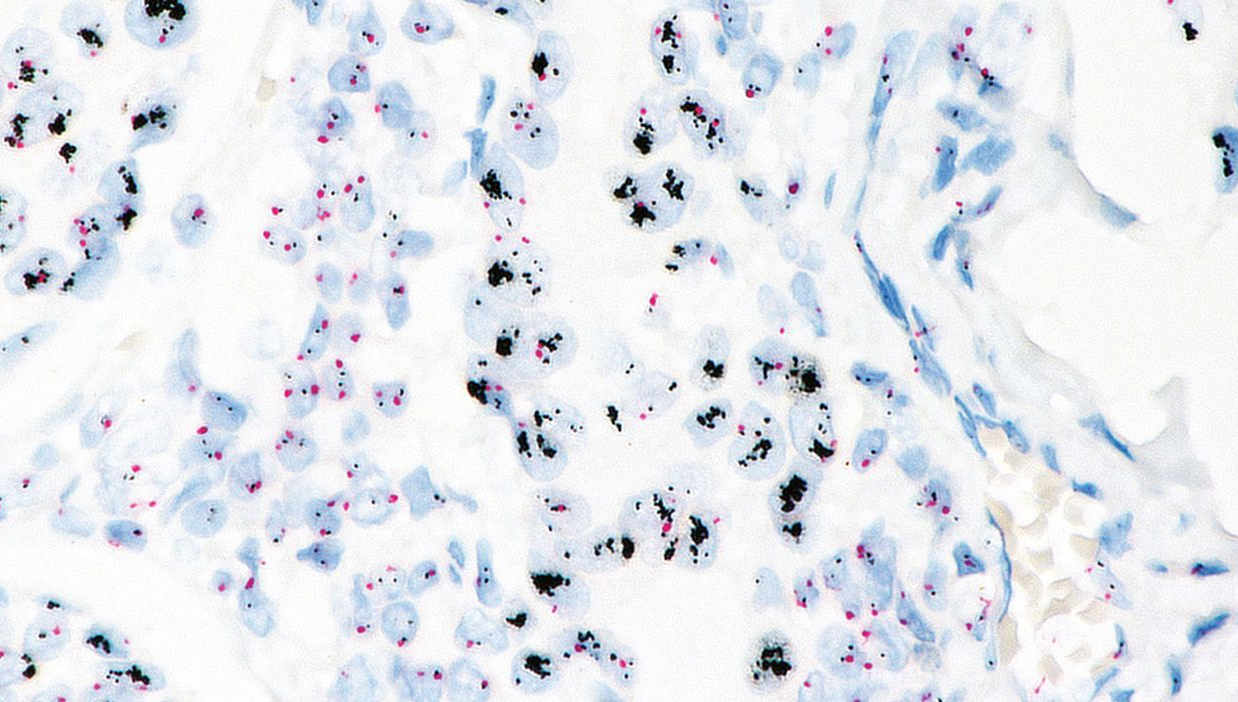

DISH染色檢查

利用石蠟包埋檢體進行免疫原位雜交(ISH)檢測。目前本實驗室提供 乳癌HER-2 DISH檢測。